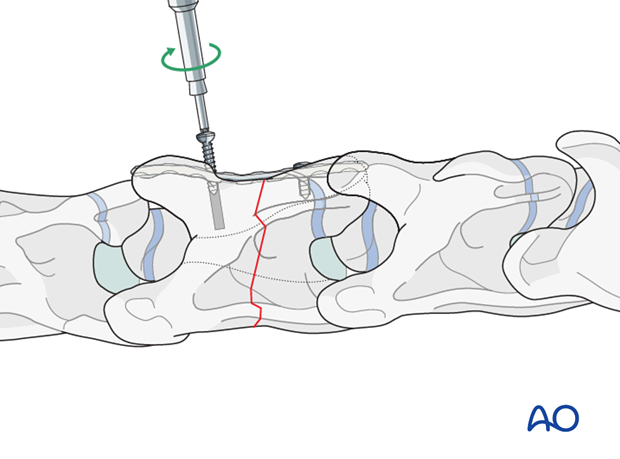

Cortex screws are used in lag fashion on both sides of the fracture to compress the fragments. The correct length of the screws is determined with the help of fluoroscopy.

Note: Attention must be paid not to damage the spinal cord.

Note: It is difficult to get a secure screw purchase in vertebral bone, particularly in foals, because of the thin vertebral cortex .

The remaining holes are filled with locking-head screws.